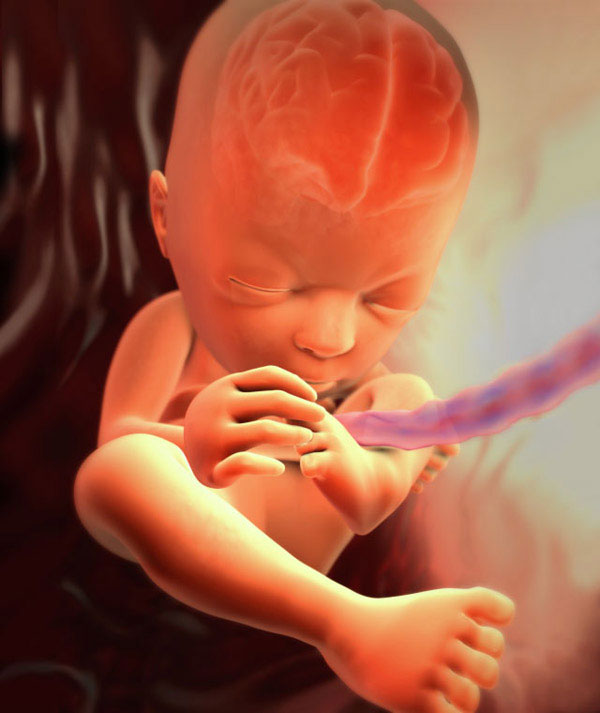

Voici à quoi ressemble le fœtus à la vingt-septième semaine:

Votre bébé grandit et commence à ressentir une certaine oppression de la cavité utérine. Les jambes et les poignées développées du bébé n'ont littéralement nulle part où les mettre. Ainsi au repos, le bébé adopte de plus en plus souvent la posture optimale pour le fœtus: tire les jambes et les bras croisés vers le ventre et la poitrine. Lorsque vient le moment de l'accouchement, c'est précisément cette position du corps (tête baissée) qui permet à l'enfant de passer normalement par le canal génital de la mère, sans complications.

Le cerveau fœtal et son système nerveux s'améliorent, ils forment de nouvelles connexions neuronales. Grâce à cela, une alternance plus ordonnée des périodes de sommeil et d'éveil du bébé commence. Par les signaux du cerveau, le fœtus fait de nombreux mouvements, comme s'il s'entraînait. Le bébé bouge ses doigts et ses membres, imite les mouvements respiratoires.

La pleine croissance du fœtus est d'environ 34 cm (du haut de la tête aux talons), pesant environ 1 kg.